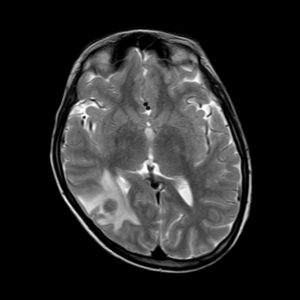

Toxoplasmosis

Lượt xem: 220» 14-06-2020 -